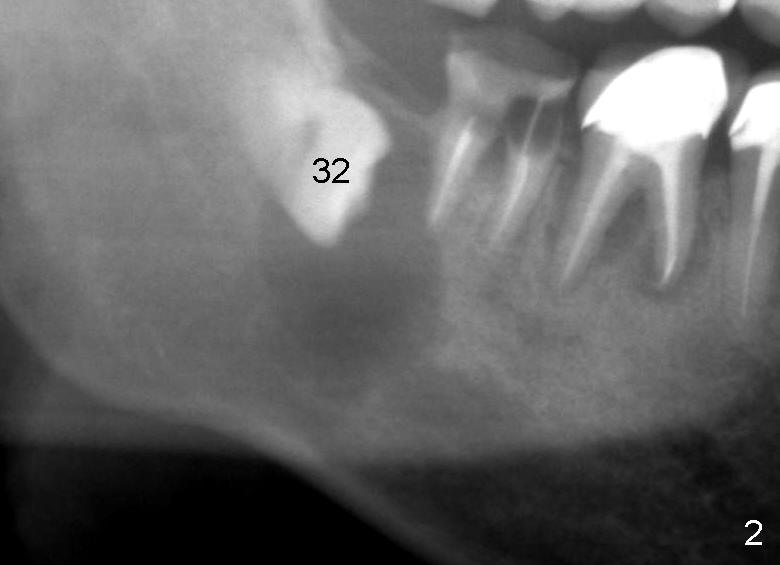

A 47-year-old man requests restoring the tooth #31 (Fig.1). It appears

that the best option is an implant. A close look reveals a possible cyst

(arrowheads) associated with #32. On the day of surgery, a panoramic X-ray

is taken (Fig.2). The cyst is to be enucleated while an immediate implant